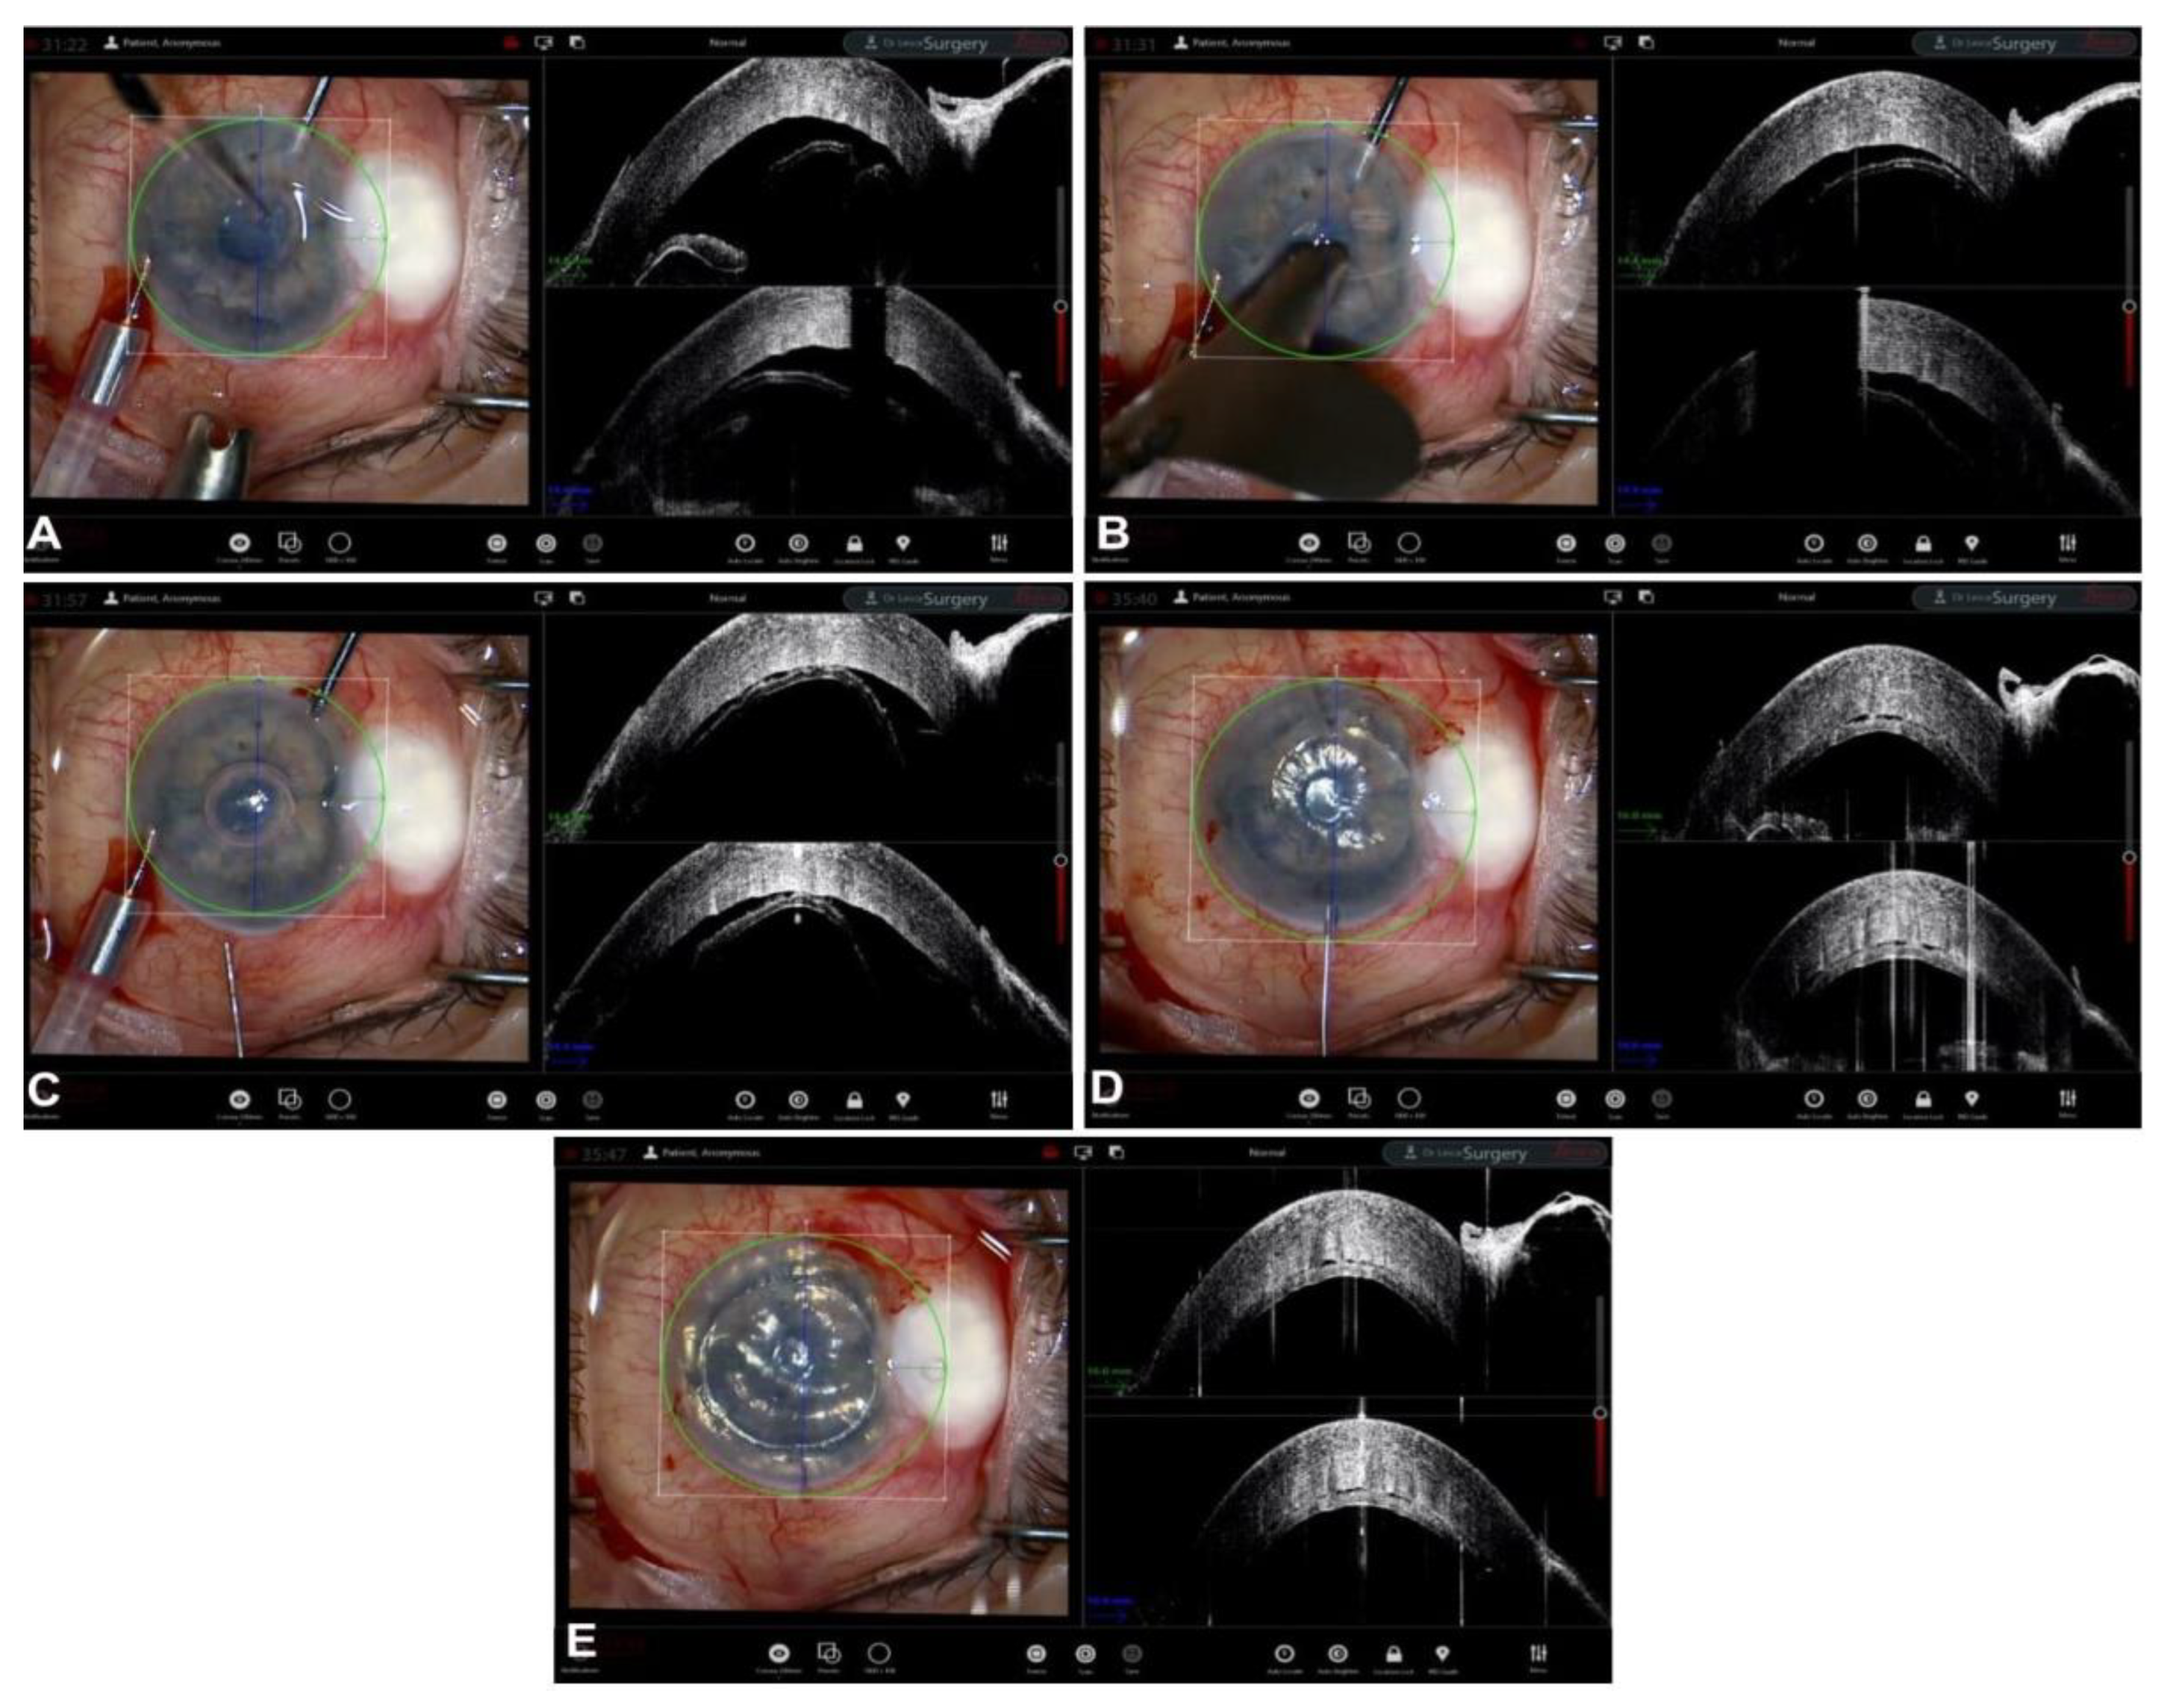

Guiding Big-Bubble Deep Anterior Lamellar Keratoplasty (BB-DALK)

4. Guiding Ultra-Thin Descemet Stripping Automated Endothelial Keratoplasy

- Pasricha, N.D.; Shieh, C.; Carrasco-Zevallos, O.; Keller, B.; Izatt, J.A.; Toth, C.A.; Kuo, A.N. Real-Time Microscope-Integrated OCT to Improve Visualization in DSAEK for Advanced Bullous Keratopathy. Cornea 2015, 34, 1606–1610. [Google Scholar] [CrossRef] [PubMed][Green Version]

- Steverink, J.G.; Wisse, R.P.L. Intraoperative optical coherence tomography in descemet stripping automated endothelial keratoplasty: Pilot experiences. Int. Ophthalmol. 2016, 37, 939–944. [Google Scholar] [CrossRef] [PubMed]

- Nowinska, A.; Wylegala, E.; Wroblewska-Czajka, E.; Janiszewska, D. Donor disc attachment assessment with intraoperative spectral optical coherence tomography during descemet stripping automated endothelial keratoplasty. Indian J. Ophthalmol. 2013, 61, 511–513. [Google Scholar] [CrossRef] [PubMed]

- Juthani, V.V.; Goshe, J.M.; Srivastava, S.K.; Ehlers, J.P. Association Between Transient Interface Fluid on Intraoperative OCT and Textural Interface Opacity After DSAEK Surgery in the PIONEER Study. Cornea 2014, 33, 887–892. [Google Scholar] [CrossRef]

- Hallahan, K.M.; Cost, B.; Goshe, J.M.; Dupps, W.J.; Srivastava, S.K.; Ehlers, J.P. Intraoperative Interface Fluid Dynamics and Clinical Outcomes for Intraoperative Optical Coherence Tomography–Assisted Descemet Stripping Automated Endothelial Keratoplasty From the PIONEER Study. Am. J. Ophthalmol. 2016, 173, 16–22. [Google Scholar] [CrossRef][Green Version]